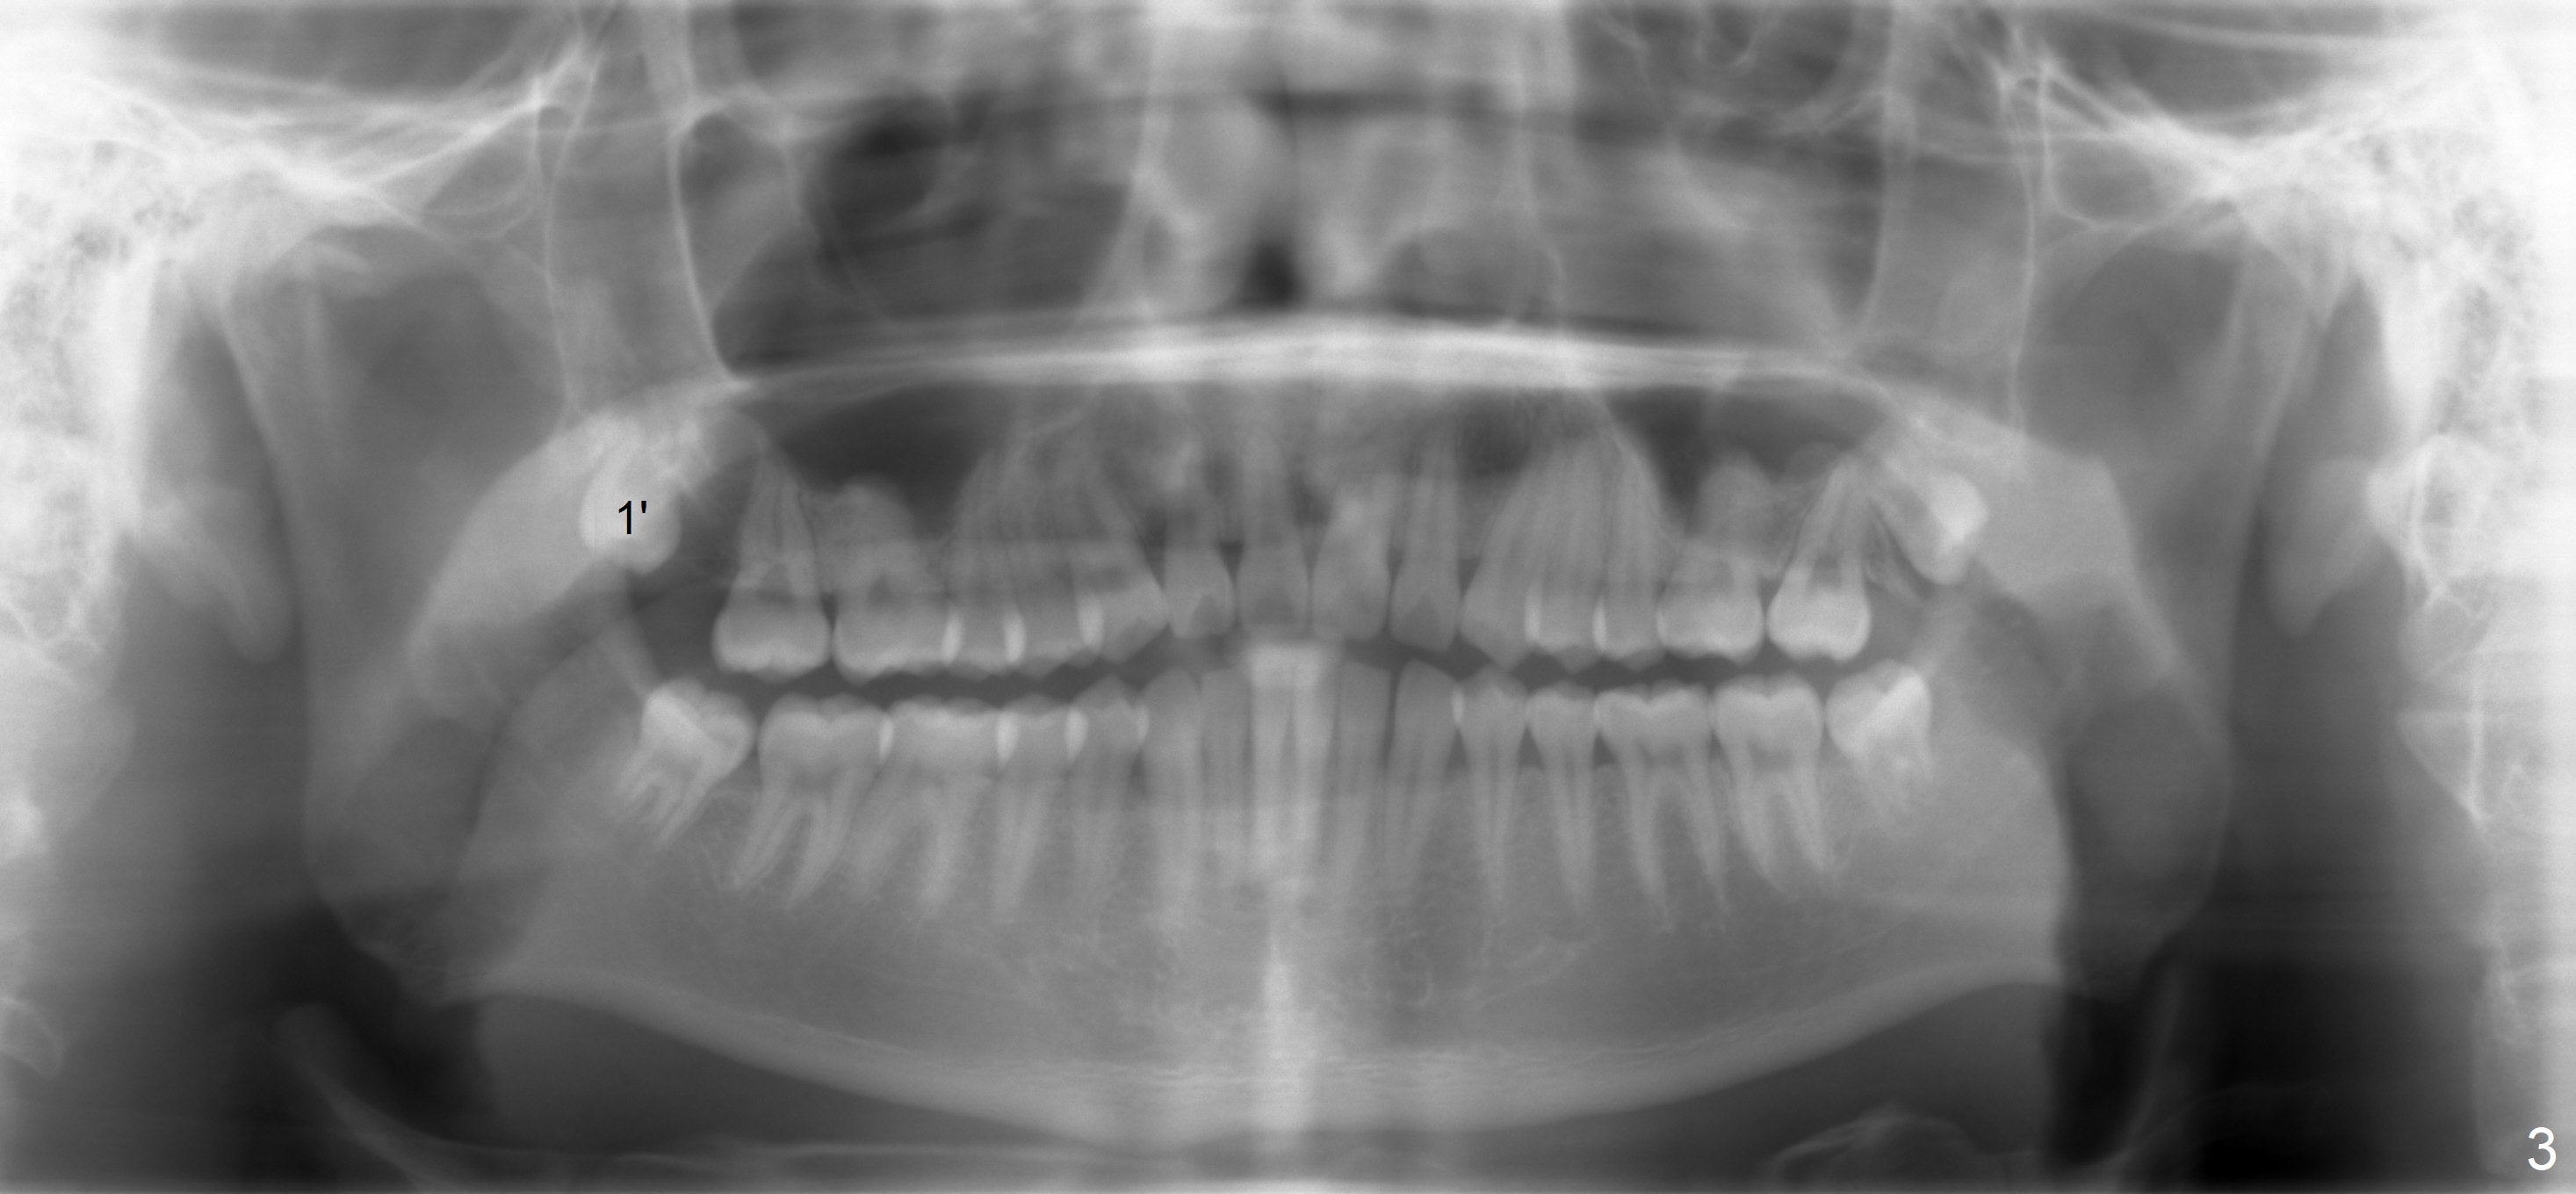

A 18 year old man has fully developing jaws.  It appears that there is enough room for 4 3rd molars to erupt normally.  In fact, the teeth #16,17,32 erupt.  Attached are pan taken 2 and 5 years ago (Fig.2,1, respectively).  I wonder whether we can take out one of the upper right 3rd molars and let the other erupt.  If the latter does not happen, #1 and 32 will be extracted.  The teeth #16 and 17 are not to be extracted.  Due to insurance limitation, the pan is not updated.  Thanks.

Now regarding this case.  No surgeon will take out wisdom teeth in a growing patient, which he is (the teeth anyway), without a current panx. So you are diagnosing from a weak position.  Regardless, you can see he has two #1 teeth--supernumerary.  It is clear the lower molars are mesial angularly impacted, with no hope of full eruption.  The upper wisdom teeth are still positioned high above the CEJ of the second molars, making removal difficult and traumatic.  But this is an old X-ray and we cannot make judgments because we know the roots are longer and the upper teeth have probably migrated more coronally.

I would plan to take all 5 teeth out.  The supernumerary tooth is above #1, so it doesn't help by removing it.  Plus even if erupted, there is no patient that brushes them on the buccal.  They all get cervical caries eventually, and are extracted as a result of discovery of the caries or a toothache.

Regarding the case u sent, I do not see 17 and 32 ever erupting and therefore I favor extraction of the opposing third molars (all three), making it a 5-tooth extraction case.

Panoramic X-ray is taken immediately post extraction of one of the upper right 3rd molars (Fig.3,3') and 20 months postop (Fi.4,4').  In fact the remaining one has erupted normally.